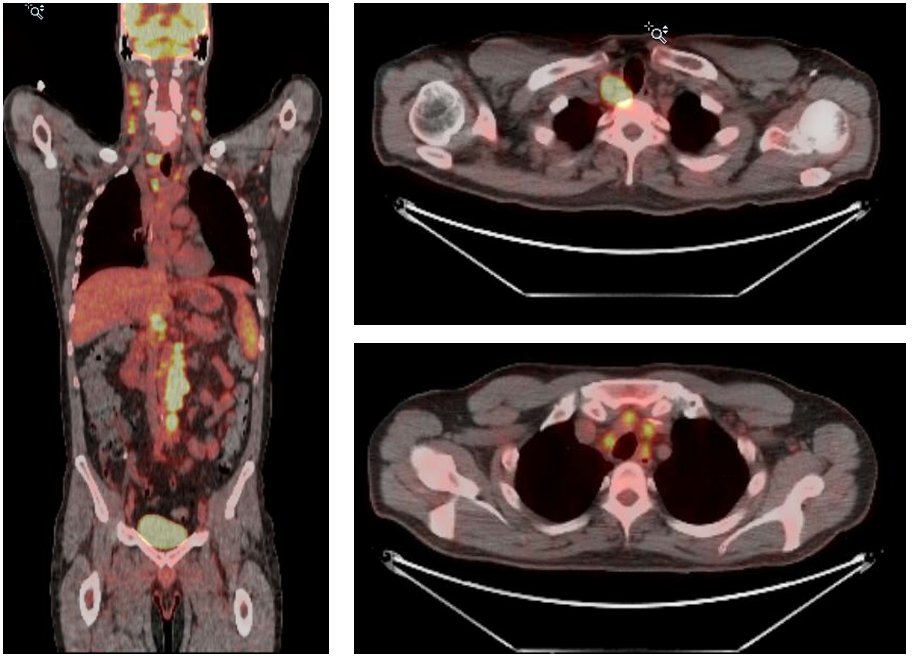

PET/CT showed multiple enlarged lymph nodes concerning for a lymphoproliferative disorder. Among these are multiple mildly enlarged LNs in the porta hepatis and gastrohepatic ligament.

3/